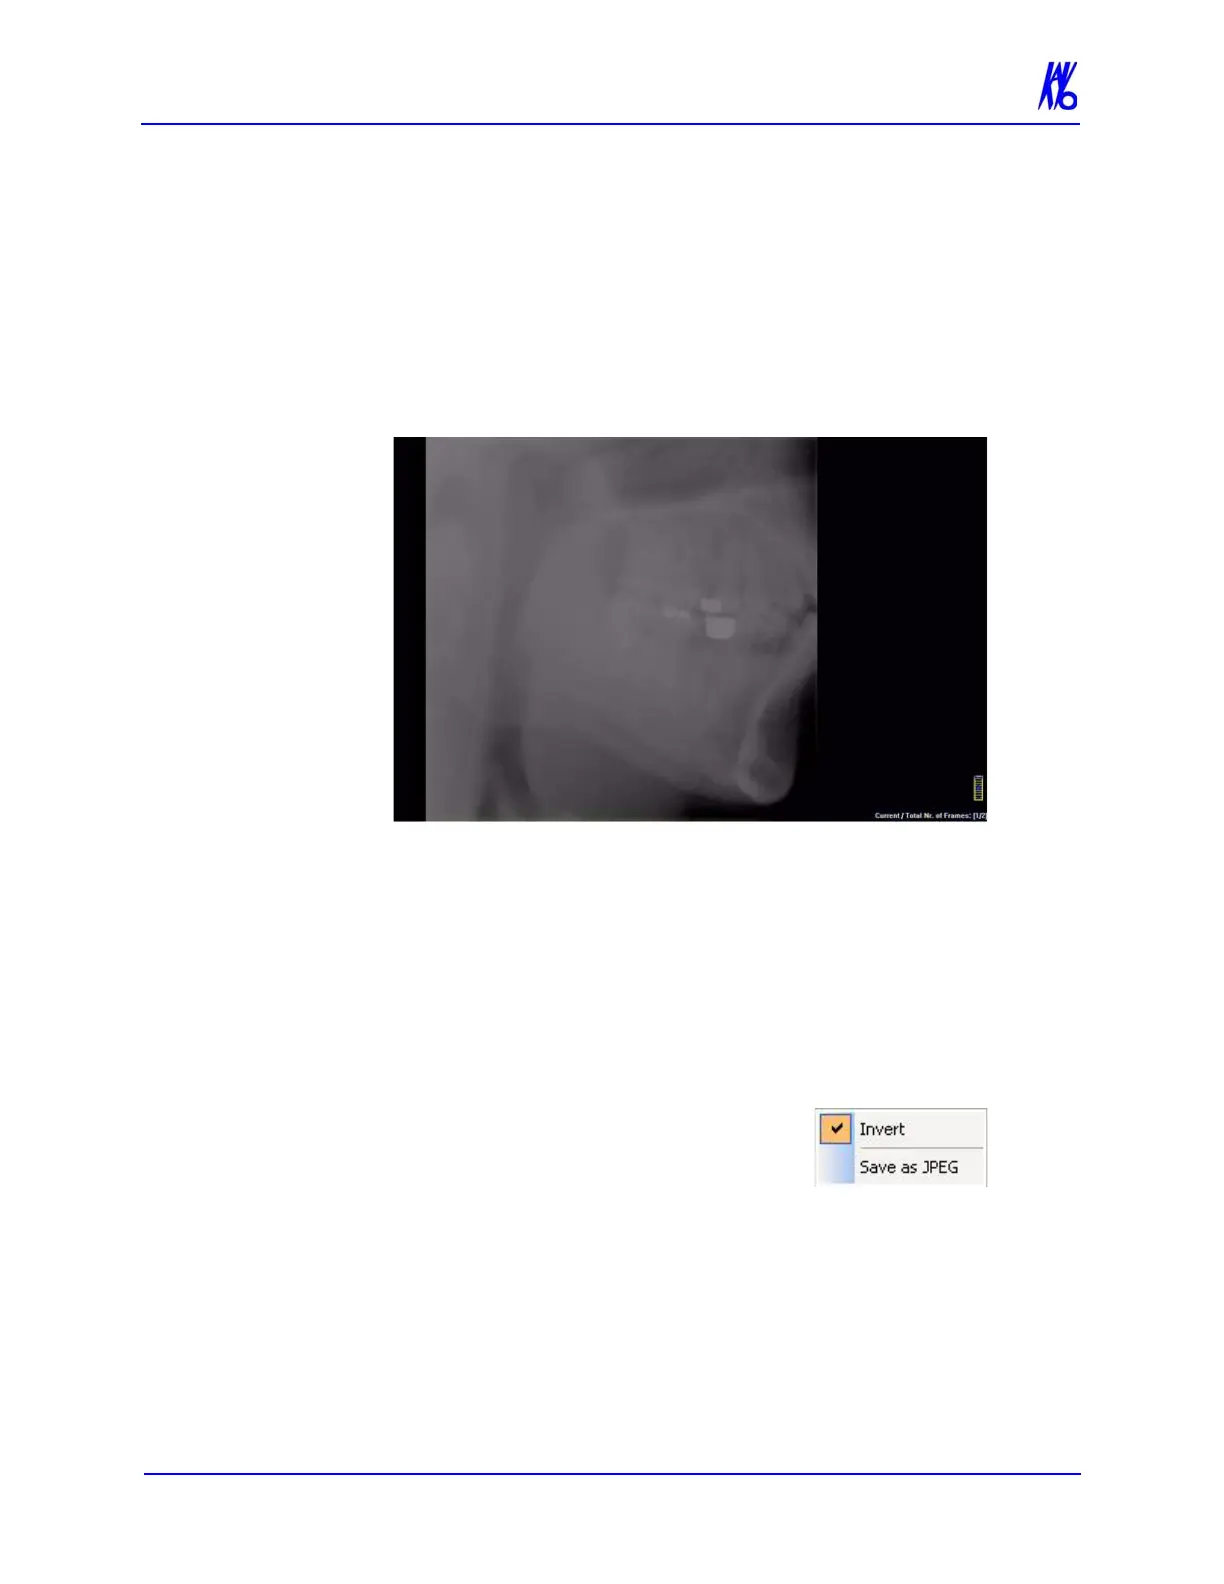

To Load Preview Frames:

1. Right-click on Raw scan and select Load Preview Frame(s).

Preview screen is displayed.

2. Image can be manipulated as follows using the features

described earlier in this chapter:

Adjust brightness and contrast

Zoom

Pan

Scroll between first and last frame

3. Right-click on the image to:

Invert - Toggle between MIP and

Radiograph.

Save as JPEG - Select a location

on the computer to save the image

as a JPEG file.